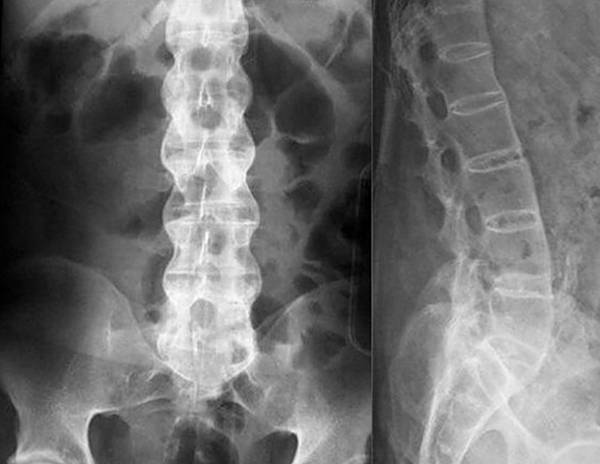

Если симптомы явно указывают на грыжу, остеохондроз или радикулит, для диагностики обычно применяют рентгенологическое исследование. Рентгенография относится к самым простым и доступным способам, к тому же, для снимка требуется совсем немного времени, в отличие от КТ, где пациент должен сохранять неподвижность достаточно долго. Для оценки состояния сосудов и мягких тканей назначают УЗИ, а при подозрении на инфекционную природу недуга обязательно проводятся лабораторные исследования крови и мочи. По полученным результатам врач подбирает больному оптимальный способ лечения.

При заболеваниях позвоночника чаще всего для диагностики применяют рентгенографию

Для достоверного установления причины нужно делать визуализацию структур области поясницы и внутренних органов. Врач назначает рентген, магнитно-резонансную, компьютерную томографию, УЗИ.